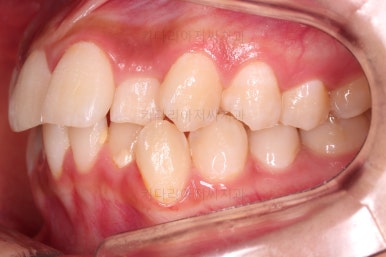

동래교정치과 초진 시의 입 안 모습이에요.

치열이 삐뚤고 덧니가 보이네요.

이번 환자분도 스스로는 보기 싫은 이유가 첫 번째였지만 사진에서도 보시다시피 양치가 잘 안되어 치석도 많고 잇몸도 부어있는 상태였어요.

그리고 앞니들이 마모가 많이 되어 있어서 각각의 치아들이 원래 형태에서 많이 변형된 것을 볼 수 있네요.

치료 종료시의 모습이에요.

총 21개월 걸렸고요.

치여링 가지런해졌고, 교합과 중앙선 등 입안의 모습이 매우 좋아졌어요.

불규칙하게 마모되어 있던 치아의 개별 형태도 약간씩 다듬어 드렸고요.